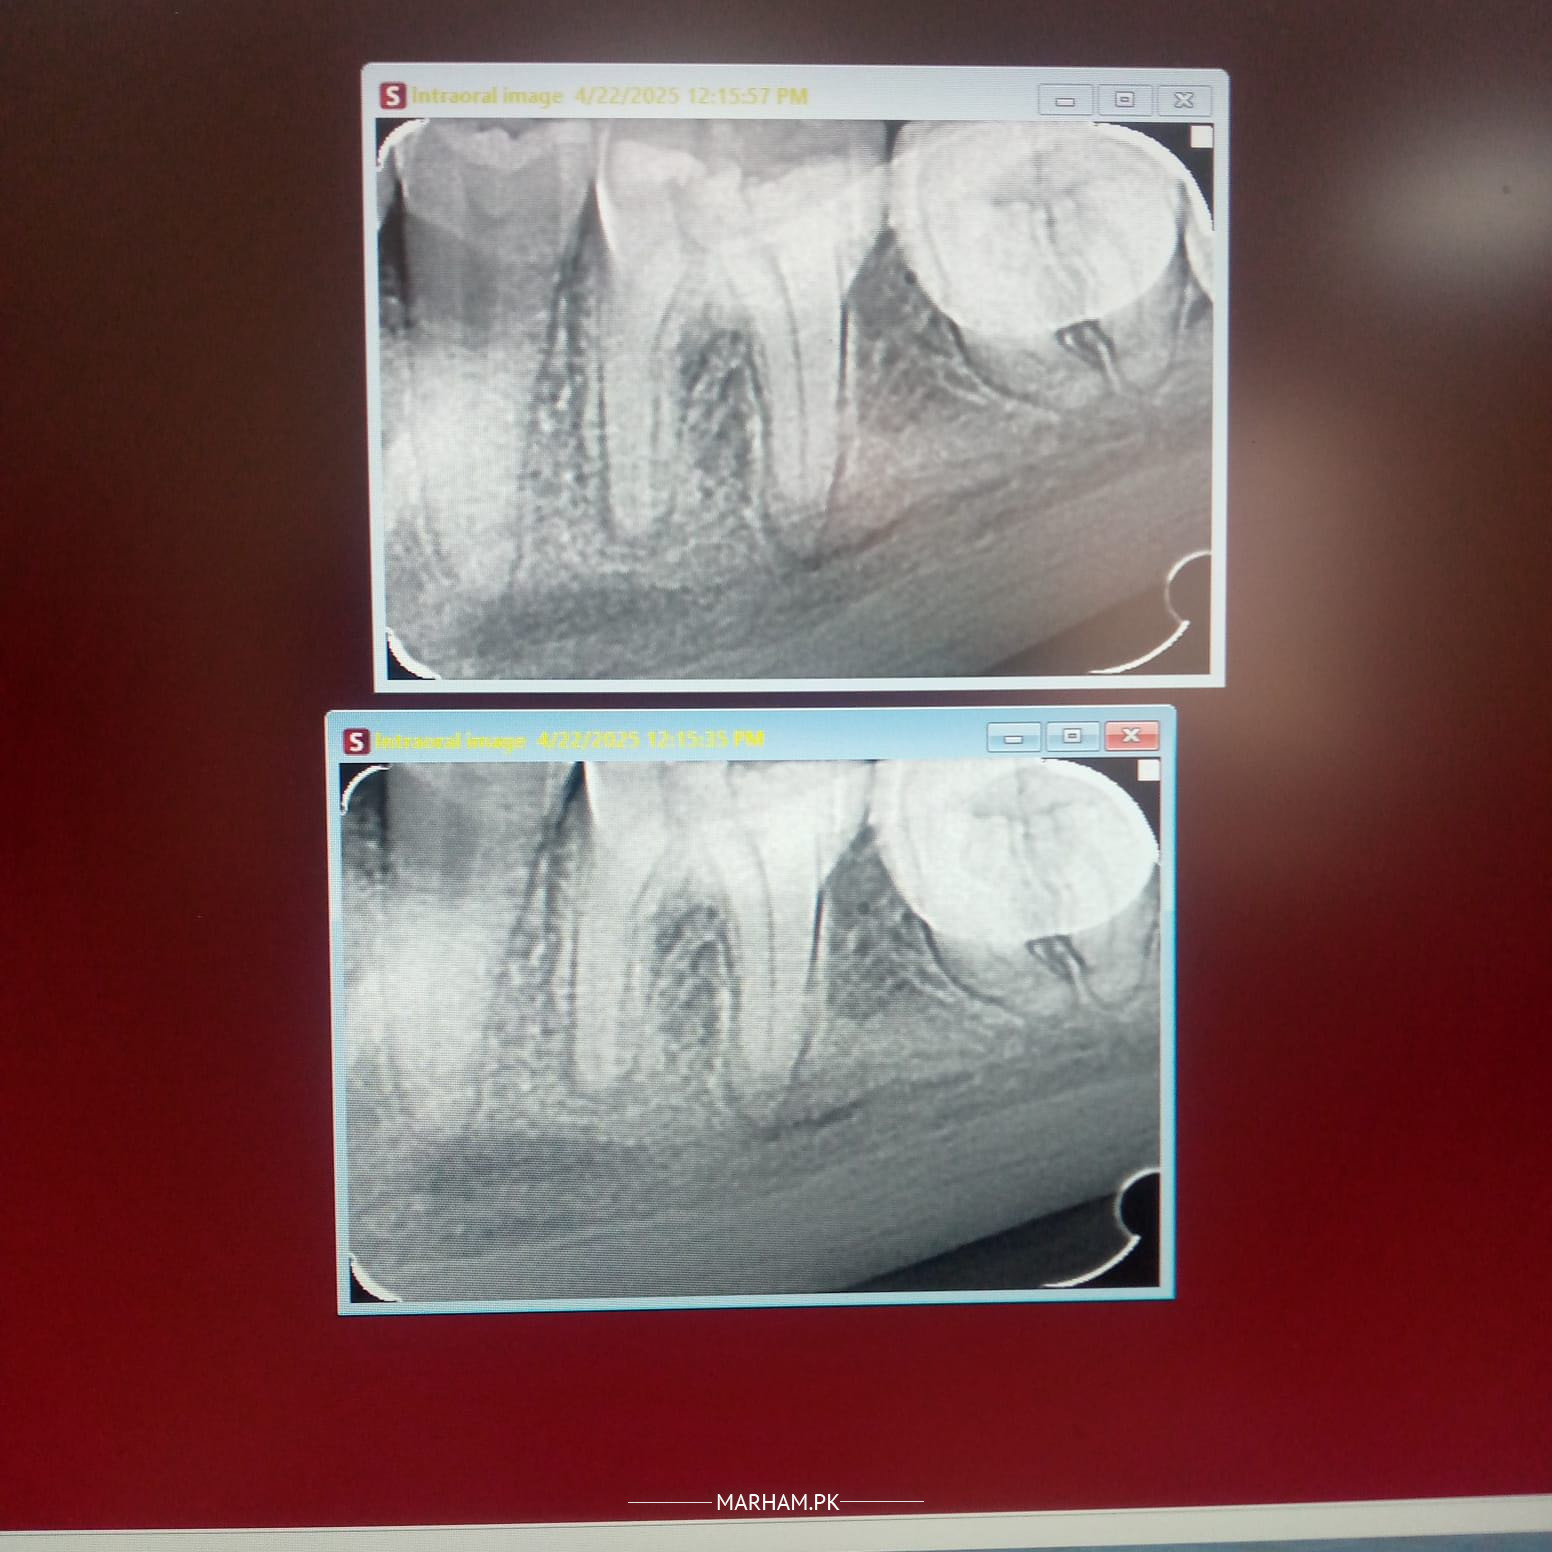

Darh main kaafi pain hai xray attach kar raha hoon kindly yeh bta dyn kiya eska treatment ho sakta hai ya darh nikalwani hogi ya dead krwani hogi?

RCT ho gee

yes treatment is possible

RCT (root canal treatment)

root canal might be possible but can only confirm after seeing clinically

Rct hoskati hai per clinically bhi dkehna hoga

yes treatment (RCT) is possible

Yes Rct hoskti ha lekin clinically dekhna parega Aqal darh ha ya USA pehla wali darh

Wisdom tooth hai or dard kate to zaroor nikalna chahiye